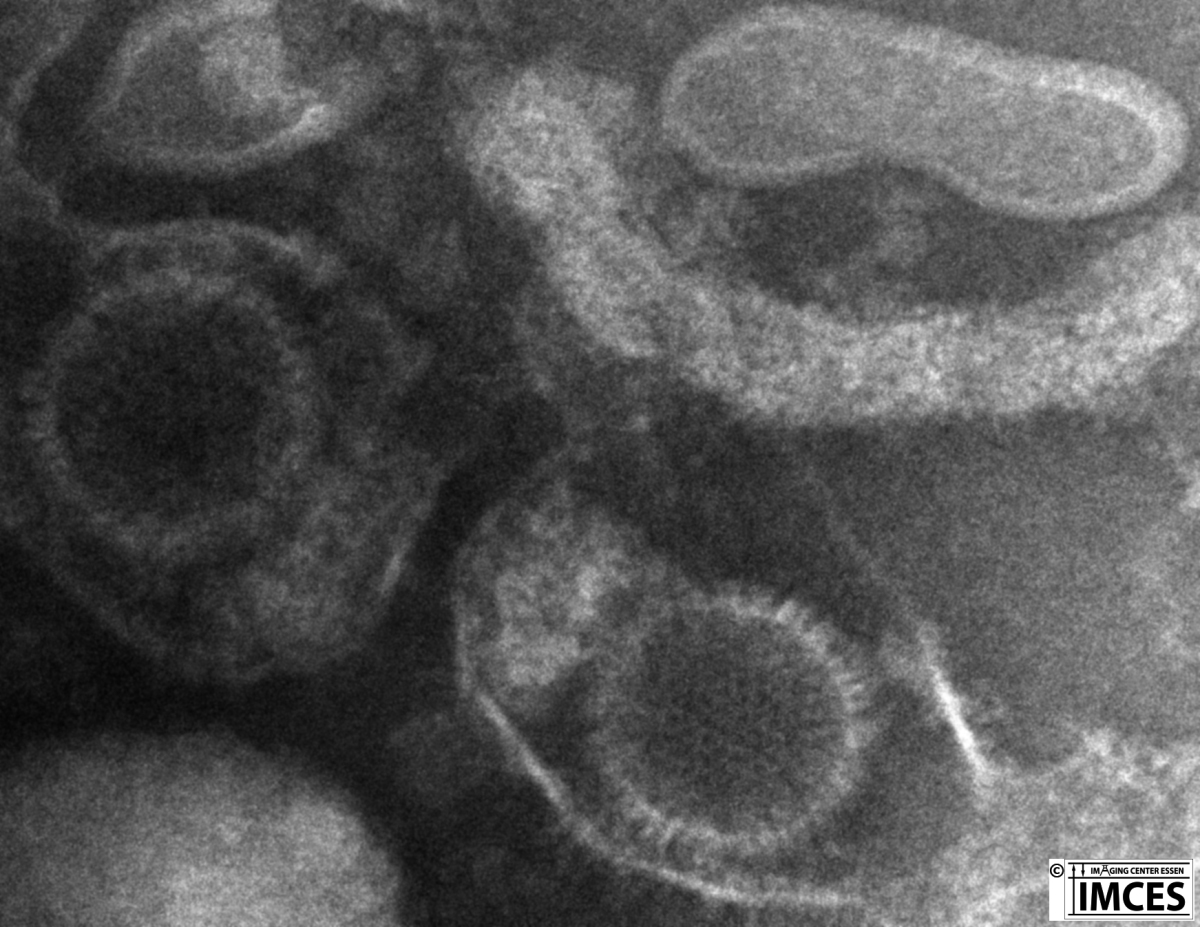

Masterarbeit S. Borkowsky als Kooperation mit Prof. M. Trilling, Institut für Virologie, UK Essen JEOL 1400 Plus TEM

Dieses transmissionselektronenmikroskopische Bild zeigt Kapside des murinen Cytomegalovirus (MCMV) nach Negative Staining. Zu beachten sind die teils DNA gefüllten Partikel, neben zwei leeren Kapsiden.